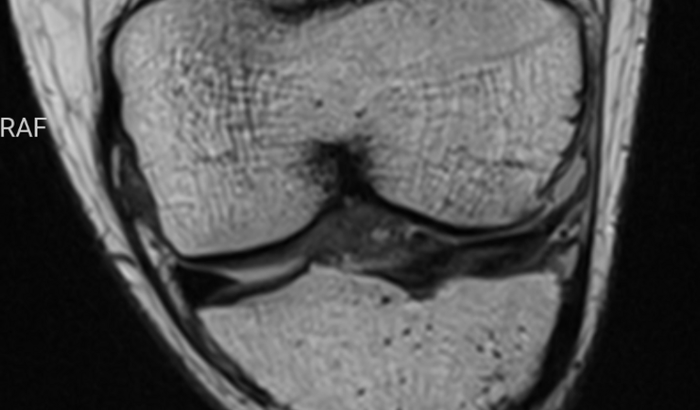

Me chamo Marlon criei essa vaquinha para pedir ajuda de vocês para conseguir fazer minha cirurgia no joelho , recentemente descobri que sofri um rompimento no ligamento lateral e no menisco do joelho esquerdo e preciso urgente fazer essa Cirurgia ,pelo SUS é muito demorada ,e o valor pago para fazer é de 7.500 mil reais .